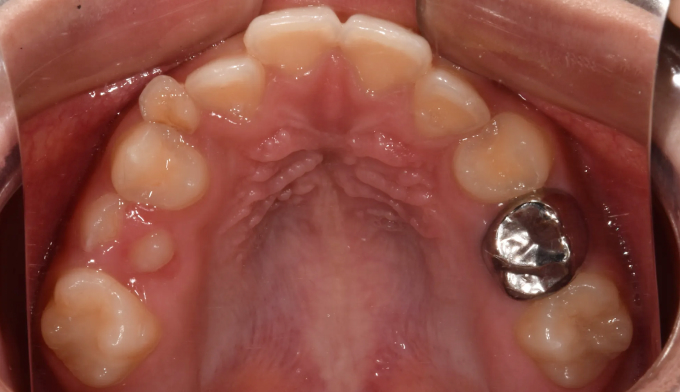

초등학교 4학년 남학생이 이가 고르지 못하고 송곳니가 나지 않는다고 합니다.

엑스레이를 찍어보니 치아가 나올 공간이 많이 부족하여 이가 고르지 못하고 송곳니가 나올 공간도 부족해 보였습니다. 정상적인 맹출 순서가 어긋나다보니 치열의 비대칭도 관찰됩니다.

약 8개월간의 공간확장치료를 통하여 이가 배열되고 송곳니가 나올 공간을 만들어주었습니다.